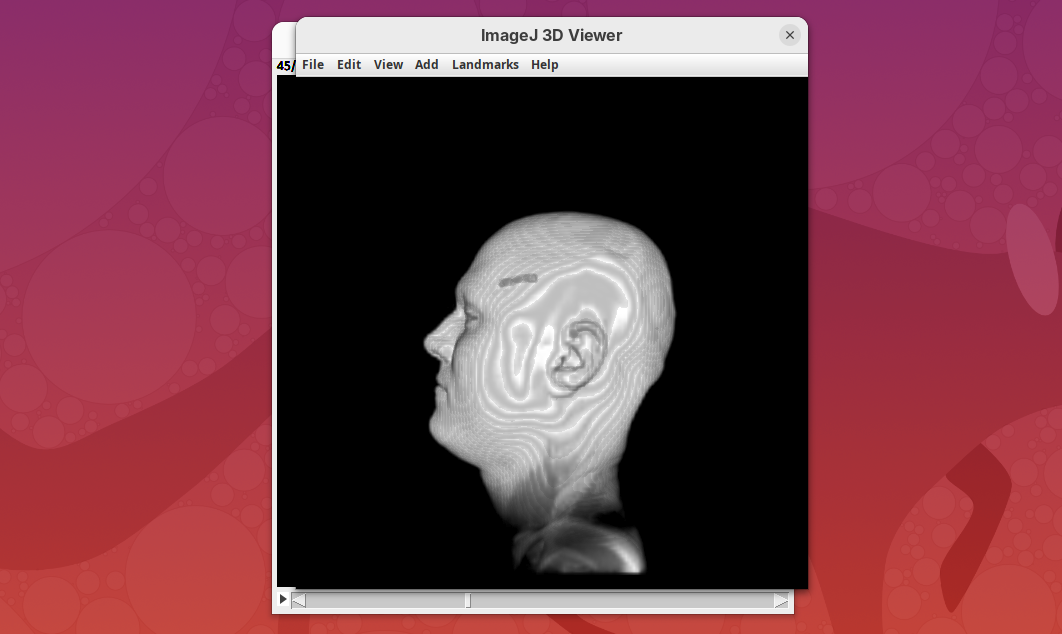

3D Viewer

The 3D Viewer (Schmid et al. 2010) is a 3D visualization plugin bundled in Fiji. It has been the default 3D rendering engine for many years and provides a good starting point for visualizing and interacting with 3D images. The interface provides some rendering and animation options, but it is possible to create more advanced visualizations and animations with code. For more details, please consult the documentation.

Here, we’ll only open our dataset with 3D Viewer for visualization.

The main interface will open.

- Explore the sample interactively.